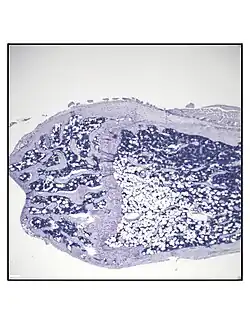

Representative distal femur histologic section of a 16-week-old healthy C57BL/6 mouse demonstrating a typical quantity of marrow adipocytes. -

Representative distal femur histologic section of a 16-week-old C57BL/6 mouse after 6 weeks of calorie restriction demonstrating an increased quantity of marrow adipocytes.